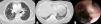

De los 29 pacientes con diagnóstico de AFB de una unidad, 3 mujeres también habían sido diagnosticadas de EPI. En 2 casos se observaba un patrón de NIC5, y en el tercero el patrón era de NII. Todas las pacientes eran mujeres de edad avanzada, no fumadoras y con antecedentes de importante exposición a humo de biomasa. La tomografía computarizada de alta resolución (TCAR) torácica de la primera paciente mostró un engrosamiento del septo interlobulillar con opacidades en vidrio esmerilado y bronquiectasias por tracción de distribución subpleural, que sugerían un patrón de NII fibrótica, y estrechamiento multifocal del bronquio del lóbulo superior derecho (fig. 1A). La segunda paciente presentaba un engrosamiento del septo interlobulillar en forma de panal y distribución basal y subpleural, sugerente de un patrón de NII (fig. 1B). En ambos casos, la prueba de la marcha de 6min indicó desaturación, y las pruebas de función pulmonar indicaron la presencia de un defecto restrictivo. Las FB mostraron pigmentación antracótica y estrechamiento/distorsión de los bronquios afectados (fig. 1C). La biopsia transbronquial de la primera paciente sugirió que se trataba de una NII, mientras que la de la segunda paciente no fue concluyente. Las tinciones y cultivos de aspirados bronquiales fueron negativos.

A) Tomografía computarizada de alta resolución torácica (ventana pulmonar), que muestra engrosamiento del septo interlobulillar con opacidades en vidrio esmerilado, bronquiectasias por tracción de distribución subpleural y estrechamiento multifocal del bronquio del lóbulo superior derecho (flecha blanca). B) Tomografía computarizada de alta resolución torácica (ventana pulmonar) que muestra engrosamiento del septo interlobulillar en forma de panal, y de distribución basal y subpleural sugerente de un patrón de NIC. C) Imagen fibrobroncoscópica que muestra pigmentación antracótica de la mucosa bronquial con estrechamiento y distorsión del segmento apical del bronquio del lóbulo superior derecho.